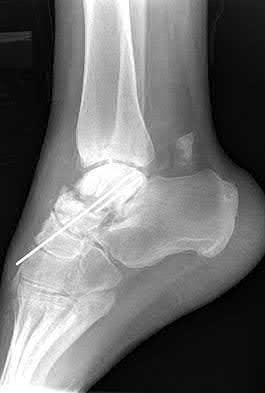

A 25-year-old female is involved in a motor vehicle collision. She presents with the isolated injury seen in Figures A through D. Her leg is swollen but her skin is intact. She has no clinical signs of compartment syndrome. Which of the following treatment options will allow for maintenance of fracture alignment and minimize the risk of soft tissue complications?

The patient presents with a closed distal third metaphyseal-diaphyseal distal tibia fracture with simple intra-articular extension. Immediate intramedullary nailing along with percutaneous fixation of the articular component provides appropriate restoration of length, rotation and alignment and minimizes the risk of wound complication.

Displaced distal third tibia fractures may be associated with simple intraarticular extension. Operative treatment of intra-articular distal tibia fractures has historically been performed with open reduction and internal fixation. Early open reduction and plate fixation of pilon fractures has been associated with high rates of infection and wound complication. In select patterns with simple articular extension, percutaneous screw fixation and medullary nailing may provide appropriate reduction with minimal soft-tissue risk.

Marcus et al. evaluated the outcomes of immediate intramedullary nailing and percutaneous fixation of simple intra-articular distal tibia fractures (AO/OTA 43 C1 and C2). The authors found excellent rates of union and alignment, however caution against broad application of this technique until more rigorous randomized studies can be performed.

Figures A and B demonstrate a distal third tibial shaft fracture with simple intra-articular extension. The axial and coronal CT cuts in Figures C and D further clarify the articular injury. Illustrations A and B demonstrate a comminuted distal third tibial fracture with simple intra-articular extension. Illustrations C and D are fluoroscopic images of the same injury after intramedullary nailing and percutaneous fixation of the articular component.